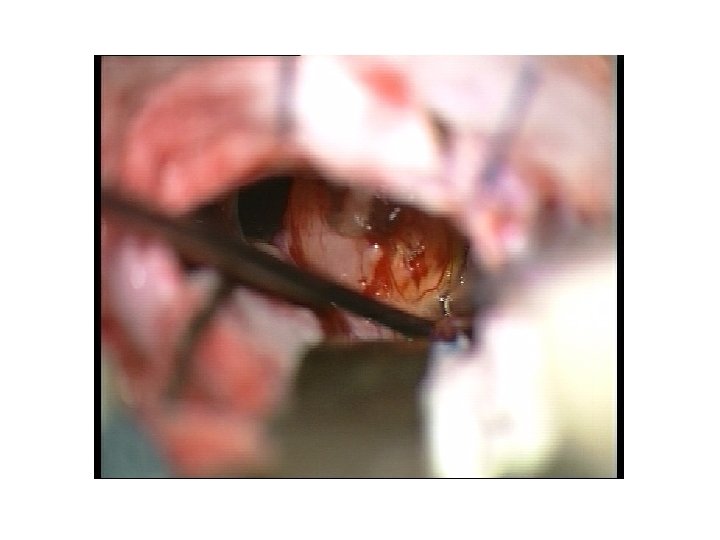

Abord rétro sigmoïde • Dissection arachnoïdienne • Aspiration endotumorale • Fraisage du CAI • Ablation tumeur endocanalaire • fermeture

Abord rétro sigmoïde • Dissection arachnoïdienne • Aspiration endotumorale • Fraisage du CAI • Ablation tumeur endocanalaire • fermeture

Abord rétro sigmoïde • Dissection arachnoïdienne • Aspiration endotumorale • Fraisage du CAI • Ablation tumeur endocanalaire • fermeture

Abord rétro sigmoïde • Dissection arachnoïdienne • Aspiration endotumorale • Fraisage du CAI • Ablation tumeur endocanalaire • fermeture

Abord rétro sigmoïde • Dissection arachnoïdienne • Aspiration endotumorale • Fraisage du CAI • Ablation tumeur endocanalaire • Stimulateur • Fermeture +++ (graisse)

Abord rétro sigmoïde • Dissection arachnoïdienne • Aspiration endotumorale • Fraisage du CAI • Ablation tumeur endocanalaire • Stimulateur • Fermeture +++ (graisse)